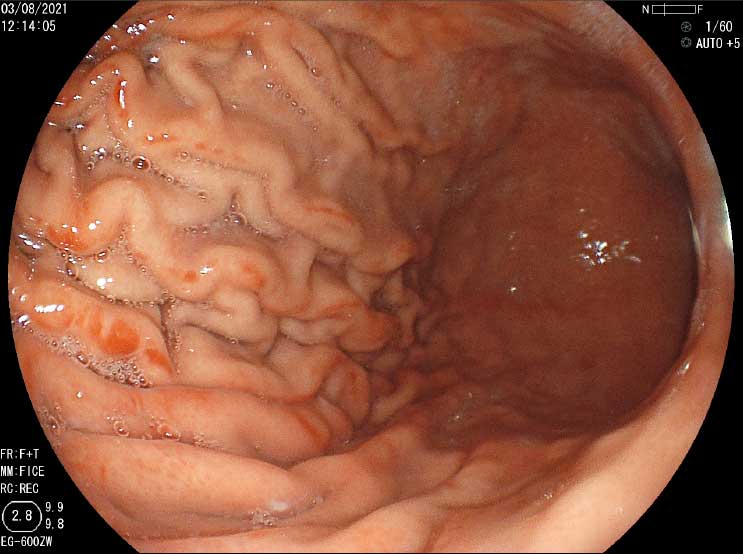

Atipia esofágica (Esofago de Barret con hernia hiatal)